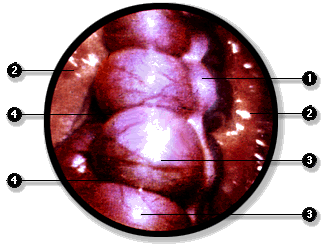

La cavidad peritoneal puede ser explorada directamente mediante la laparoscopía. En este examen se introduce un instrumento óptico, el laparoscopio, y se inyecta gas en la cavidad peritoneal para separa las hojas visceral y parietal del peritoneo. De esta manera es posible recorrer la cavidad e incluso realizar, bajo visión directa, ciertas intervenciones quirúrgicas que no requieren de un abordaje amplio de la cavidad abdominal.